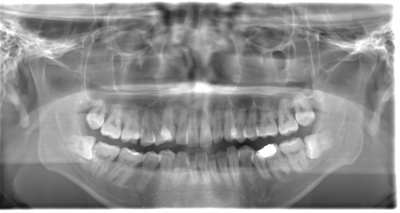

CASE 4

| 年齢・性別 | 30代・男性 |

| 主訴 | 左上親知らず抜きたい |

| 抜歯期間 | 15分 |

| 抜歯費用 | 約2,000円(保険内) 別途CT撮影で3,000円 |

| 抜歯内容 | 左上の親知らず抜歯 |